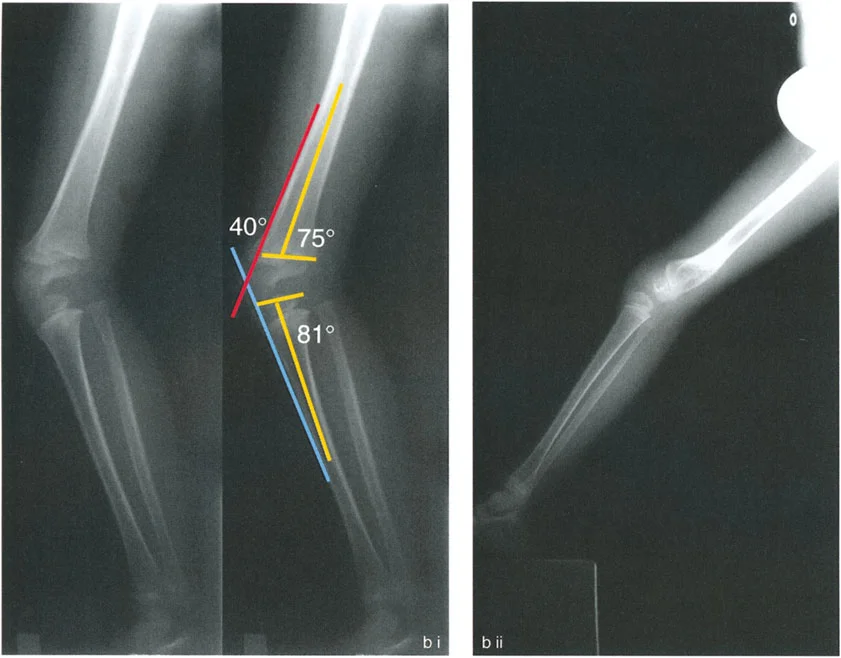

تُعد الأشعة التصويرية ضرورية لتأكيد التشخيص وتحديد مدى الضرر وموقع التشوهات العظمية بدقة:

- الأشعة السينية (X-rays):

- الأشعة الأمامية الخلفية (AP View) والجانبية (Lateral View): تُظهر حالة العظام، تآكل الغضروف (يُلاحظ كضيق في المسافة المفصلية)، وجود نتوءات عظمية (Osteophytes)، وأي تشوهات عظمية واضحة.

- الأشعة السينية الطويلة للطرف السفلي بالكامل أثناء الوقوف (Standing Long-Leg AP View): تُعد هذه الأشعة حاسمة لتقييم المحاذاة الميكانيكية للطرف السفلي بأكمله. تُظهر بدقة درجة الانحراف الأفحج (Varus) أو الأروح (Valgus) وتساعد في تحديد مركز دوران التشوه (CORA).

- الأشعة الجانبية الطويلة للطرف السفلي بالكامل أثناء الوقوف في أقصى بسط (Standing Long-Leg Lateral View in Maximum Extension): تُستخدم لتقييم تحدد حركة الركبة (FFD) والركبة الارتدادية (Recurvatum)، وتحديد ما إذا كان التشوه عظميًا أو ناتجًا عن تقلص في الأنسجة الرخوة.

تصحيح تحدد حركة الركبة (Flexion Deformity - FFD)

تحدُّد حركة الركبة هو عدم القدرة على مد الركبة بالكامل. يمكن أن يكون سببه عظميًا أو ناتجًا عن تقلص في الأنسجة الرخوة.

- التشخيص الدقيق: يجب تحديد ما إذا كان تحدد الحركة ناتجًا عن تشوه عظمي (تقوس أمامي في الفخذ أو الساق) أو تقلص في الأنسجة الرخوة (الأوتار الخلفية، محفظة المفصل).